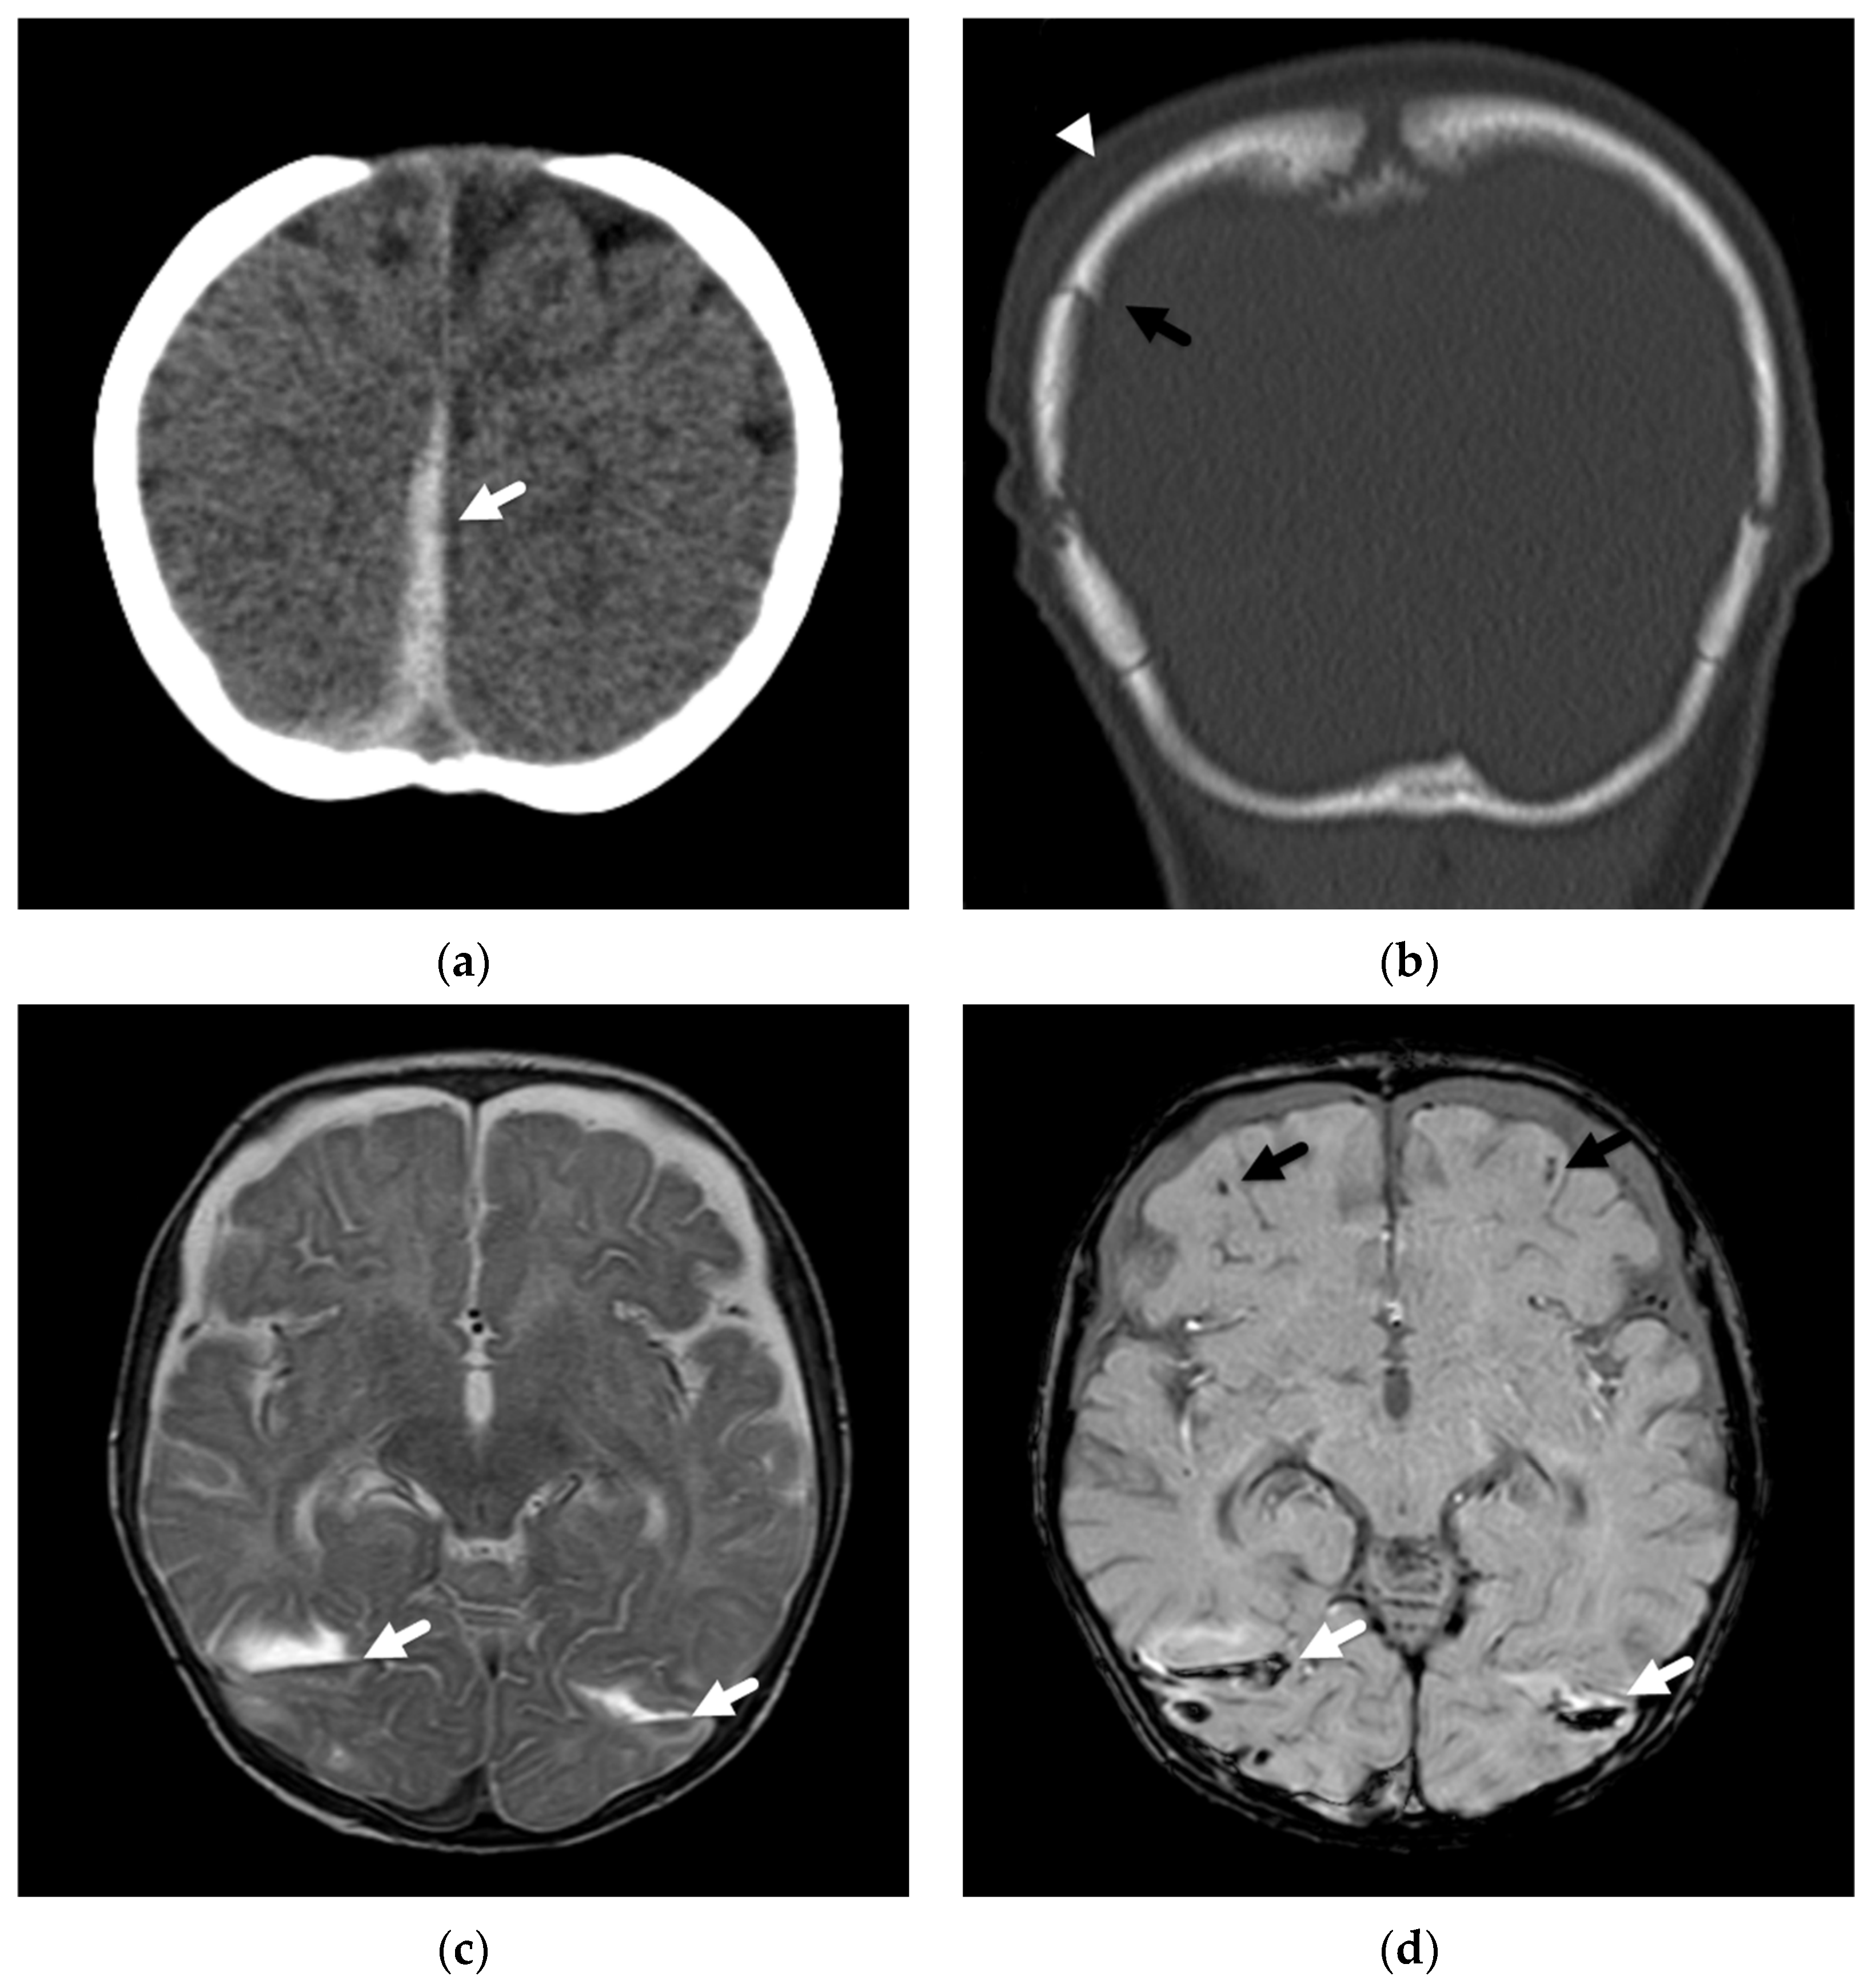

2. Patterns of Diffuse Parenchymal Insults

3. Imaging of Diffuse Insults